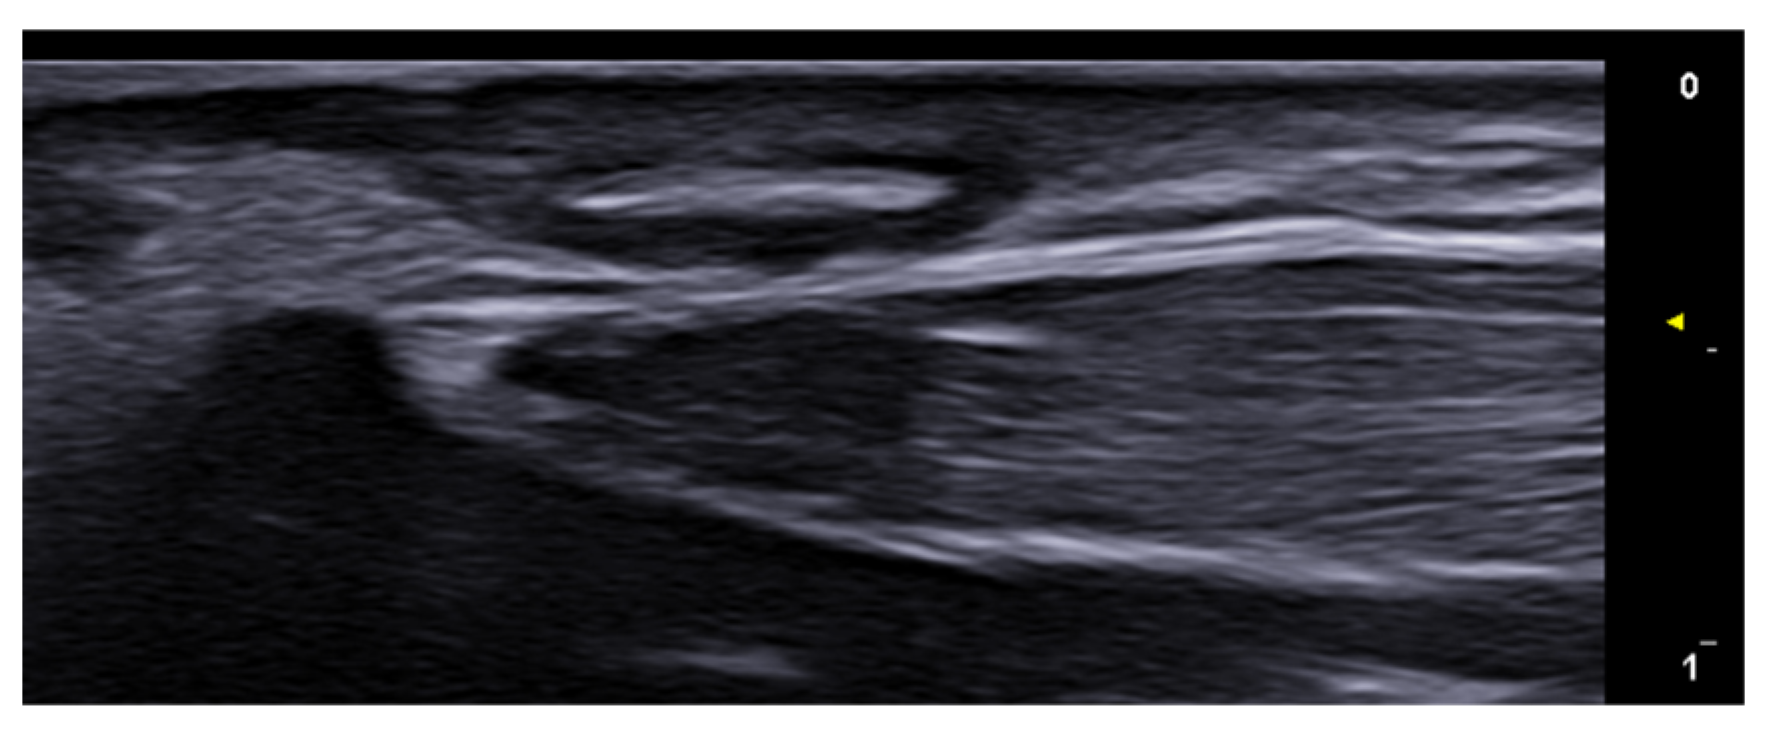

- Sechi, A.; Starace, M.; Piraccini, B.M.; Wortsman, X. Ultrasound Features of Onychopapilloma at High-Frequency and Ultra-High Frequency. J. Ultrasound Med. 2024, 43, 71–76. [Google Scholar] [CrossRef] [PubMed]